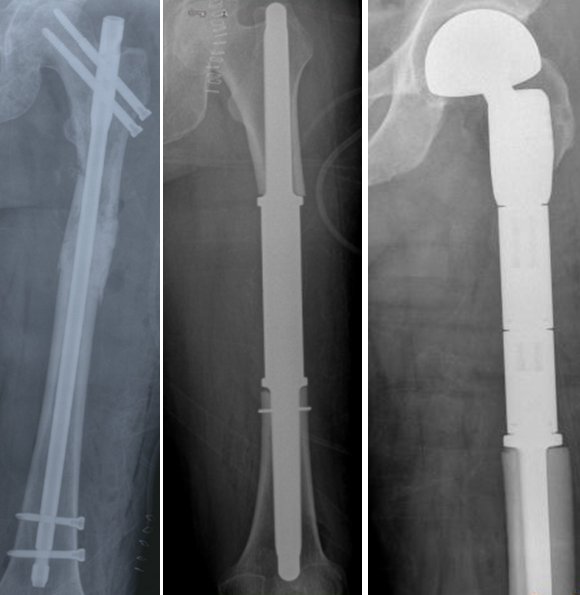

Şimdiye kadar anlattıklarımız kemik yada yumuşak dokunun kendisinden primer olarak kaynaklanan lezyonlardı. Metastazlar ise vücutta var olan kanserli bir dokudan (ör: akciğer kanseri, meme kanseri, böbrek kanseri yada prostat kanseri gibi) ayrılan kötü huylu hücrelerin kan yolu ile kemiklere gelmesi ve burada kitleye neden olmasıdır. Metastazlar genellikle orta-ileri yaş grubunun rahatsızlıklarıdır. Burada hasta büyük oranda kanser olduğunu zaten biliyordur yada kanser tedavisi almaktadır. Örneğin akciğer kanseri olduğu bilinen bir hastada son zamanlarda başlamış olan kalça, bacak , omuz, dirsek yada bel ağrıları ön planda metastaz oluştuğunu akla getirir (resim-24). Metastazlar hızlı ilerleyen kötü huylu lezyonlardır. Tedavileri çabuk şekilde yapılmalıdır. Aksi halde şiddetli kemik ağrıları ortaya çıkar ve sonunda patolojik kırık meydana gelmesi kaçınılmaz olur. Bu durumda tedavi daha da güçleşecektir.

Resim 25

Kemik metastazlarının tedavisinde radyoterapi yada cerrahi tedavi ön plandadır. Eğer hastada patolojik kırık yada patolojik kırık tehditi yoksa radyoterapi tek başına yeterli olabilir. Ancak patolojik kırık gelişmişse yada kırık gelişmek üzereyse (patolojik kırık tehditi) cerrahi uygulanmalıdır. Amaç, hastanın ağrılarını dindirmek ve bir an önce günlük aktivitelerini kazandırarak hayata geri döndürmektir. Ameliyatta tümörlü alan çıkartılır ve oluşan kemik defekti ise implant kullanılarak giderilir (resim-25)..